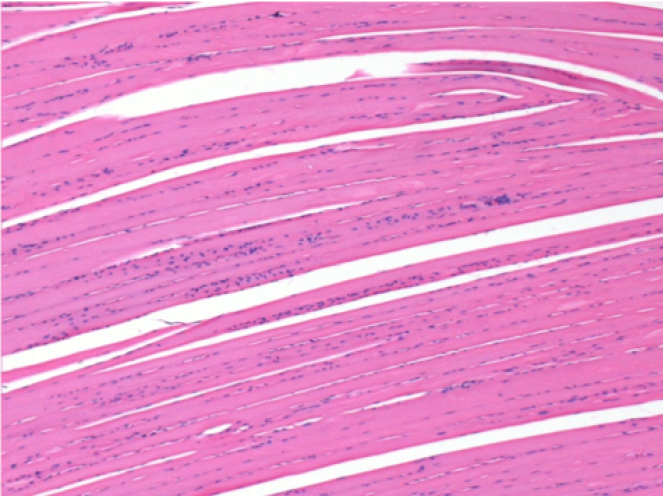

1 month after Endopeel Injection

1 month after Endopeel Injection 0.1ml in the right pretibial muscle.

What is seen in black on the pictures is not a necrosis like could imagine some scientifics !

In fact, 4 conclusions have to be taken in consideration

- an artefact of coloration

- an absence of necrosis

- an apoptosis

- a bioregenerative process

L : Control-100xD30

R:100xD30

R :400xD30